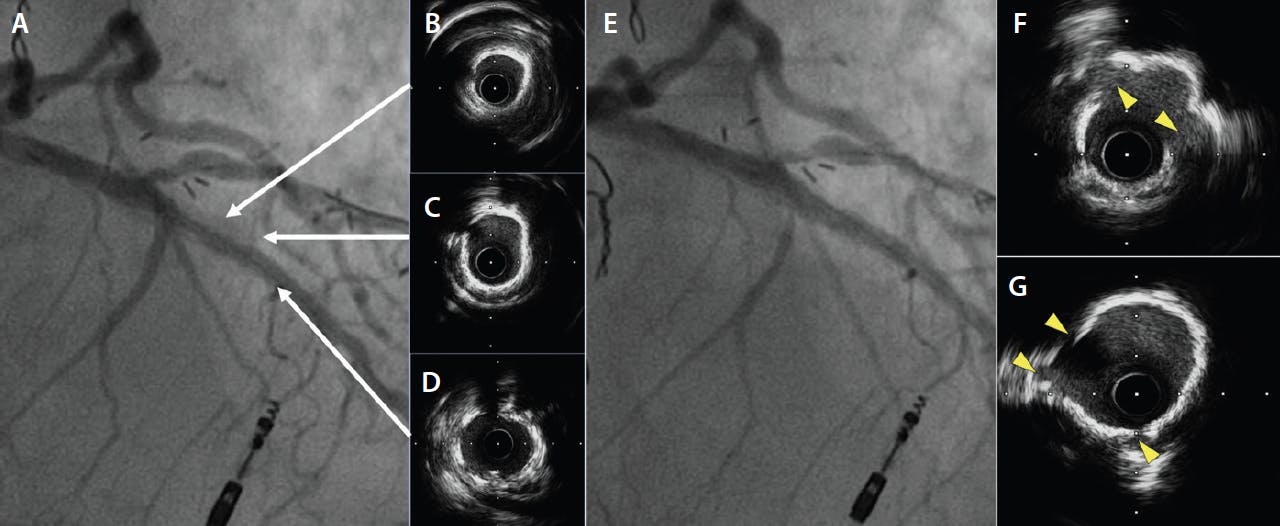

Calcified lesions.  The efficacy of a cutting balloon for the treatment of calcified lesions has been demonstrated in various studies. In moderate and severe coronary calcific stenosis, cutting compared to conventional angioplasty can achieve a larger size and better immediate minimal lumen area.5 Cutting can be used alone or in combination with other plaque-debulking devices. It has proven efficacy with rotational atherectomy, and optical coherence tomography (OCT) studies in severely calcified lesions suggest that calcium fracture is more often associated with rotational atherectomy followed by a cutting balloon compared with rotational atherectomy followed by conventional balloon predilation before stenting (Figure 2). Moreover, a greater stent expansion with the cutting balloon has been demonstrated.6 In calcified lesions, the cutting balloon can be advanced, but in some cases, a certain degree of resistance can be encountered; for this reason, we recommend an initial predilation with a noncompliant balloon to pave the way. When dealing with extensive and thick calcifications, we acknowledge the need of other technologies, such as rotational atherectomy and lithotripsy.

Figure 2. Severe calcified lesion of the mid left descending coronary artery not expandable after rotational atherectomy with a 1.5-mm burr (A). Baseline IVUS demonstrated deep circumferential calcium (B-D). The lesion was dilated with a super high-pressure balloon (OPN 3.0 at 35 atm) and with a 3- X 10-mm cutting balloon inflated at 26 atm. The angiographic result was satisfactory (E), and the postprocedure IVUS showed cuts on the calcium surface (yellow arrows) with nice lumen gain (F, G).